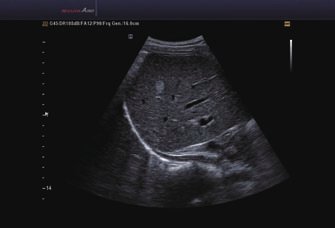

Das Samsung Accuvix A30 ist ein hochwertiges Ultraschallsystem, das mit seiner 3D-Technologie herausragende Ergebnisse ermöglicht. Das Sonographiegerät besitzt 5 Sondenanschlüsse und ist mit 20 unterschiedlichen Schallköpfen kompatibel. Mit dem A30 können Schallköpfe vom Typ Konvex, Mikrokonvex, 3D-Konvex, CW, Phased Array, Linear und Endokavitär verwendet werden. Bei zwei der Sonden handelt es sich um S-VUE Ultraschallsonden, die durch ihre höhere Bandbreite noch feinere Scans erzeugen.

Das Ultraschallsystem hebt sich besonders durch seine 3D-Technologie wie die Face Auto Detection für detaillierte Ultraschallbilder von Föten oder das Volume Shade Imaging, das sich auf die lebensnahe Darstellung von Schattierungen und Hauttönen fokussiert, ab. Mit weiteren wertvollen Technologien wie dem ElastoScan™ werden Tumore schneller erfasst und durch die HD Volumen Bildgebung sowie das DMR+™ eine erstklassige Bildqualität erzielt.